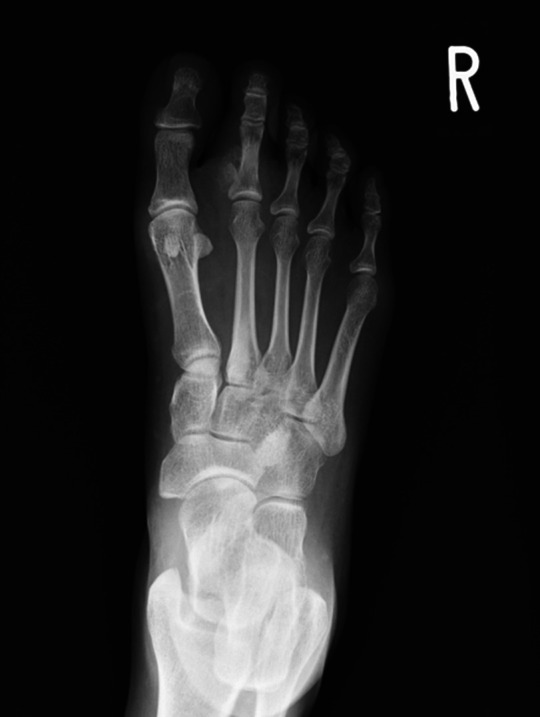

Florid Reactive Periostitis of the Toe.

脚趾弗洛里反应性骨膜炎